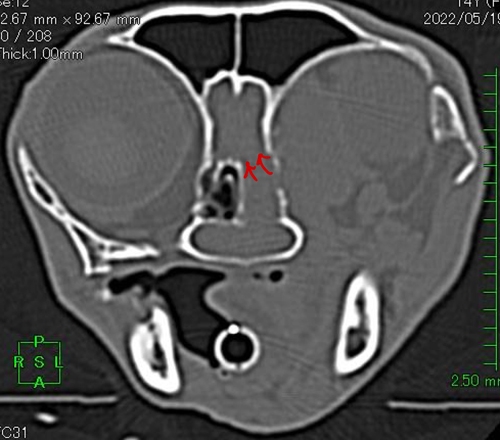

鼻腔内には腫瘍が充満しており、左眼窩骨(目と鼻を区切る骨)が溶けていて眼窩内(目がおさまってる空間)に浸潤(侵入)しています(赤の斜線部分)。そのため左目は外側に押されています!!↓↓

さらに脳と鼻を区切る骨(篩板)も溶けていて頭蓋内浸潤も疑われました(赤矢印)。↓↓